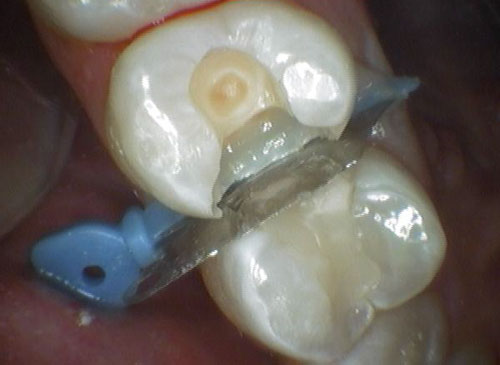

覆盖非烂牙的其余部分

当*醉药麻**开始作用于您的牙齿时,嘴的其余部分被橡皮障覆盖。橡皮障是一种橡胶板,固定在金属框架上并放入口中。在片材中形成小孔,并将其向下拉伸至待填充的牙齿。我们的想法是,它可以防止任何填充材料或牙屑进入您的喉咙或口腔,并帮助牙医专注于需要填充的牙齿。